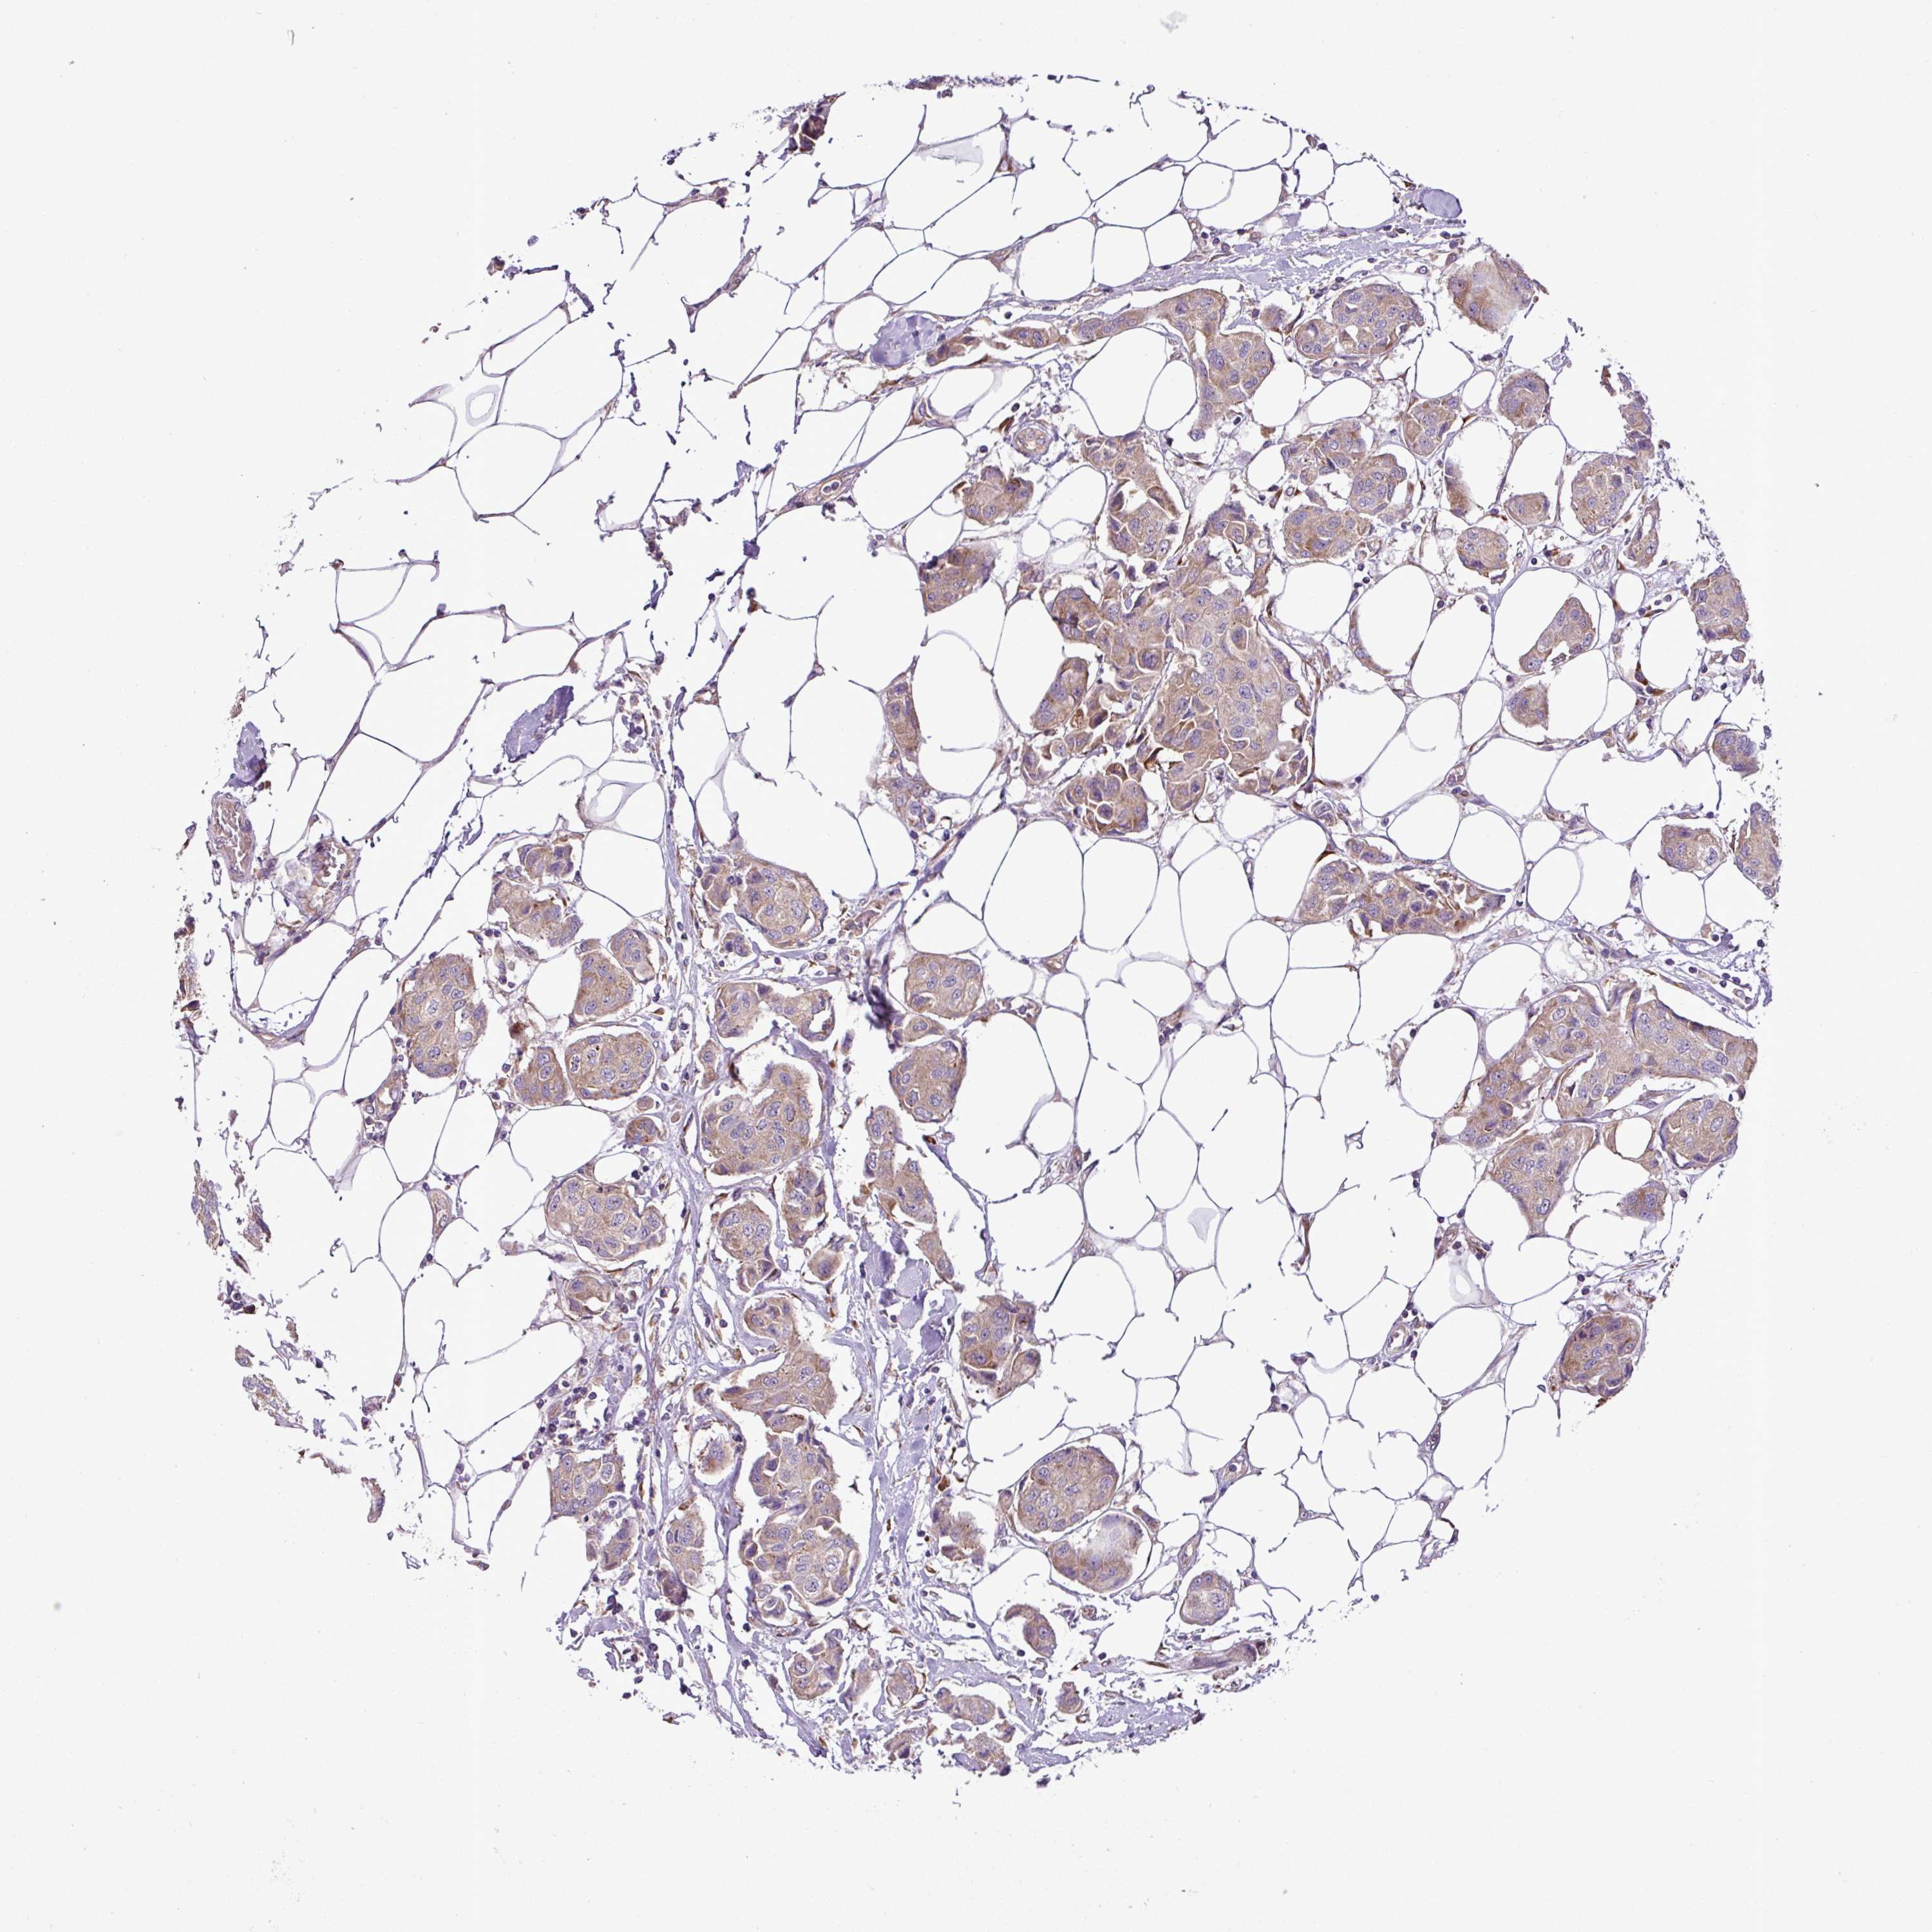

CANCER BREAST CANCER Show tissue menu

BRCA TCGA BRCA VALIDATION PROTEIN EXPRESSION